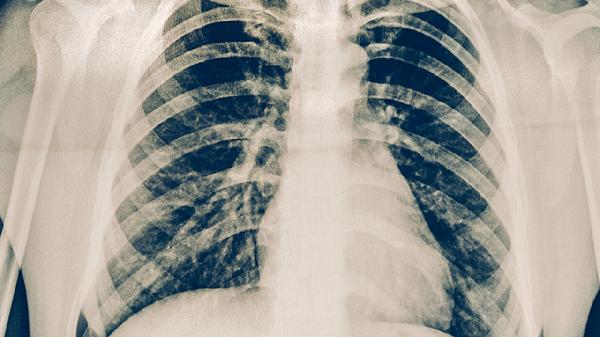

肋骨中间三角区有个骨头凸起可能是剑突突出、肋软骨炎或胸骨畸形等引起。剑突是胸骨下端的小骨性突起,部分人群因发育差异可能较为明显;肋软骨炎可导致局部肿胀;胸骨畸形如鸡胸也可能表现为骨性隆起。若伴随疼痛、红肿或影响呼吸需及时就医。

剑突是胸骨末端的软骨结构,正常成年后逐渐骨化,部分人因个体差异可能突出明显且无病理意义。长期伏案工作或姿势不良可能加重局部应力,导致触诊时更易察觉。肥胖者因皮下脂肪覆盖可能不易发现,而消瘦人群更易触及。生理性剑突突出通常对称且质地坚硬,按压无疼痛感。

肋软骨炎多由外伤或反复劳损引发,表现为肋骨与胸骨连接处肿胀压痛。炎症反应可导致局部组织增生,形成肉眼可见的骨性隆起。患者常主诉咳嗽或深呼吸时疼痛加剧,皮肤表面可能出现轻微发红。胸骨畸形中的鸡胸表现为胸骨前凸,多与青少年发育期维生素D缺乏有关,严重者可影响心肺功能。

日常应避免对突出部位过度按压或撞击,睡眠时选择软硬适中的床垫减轻局部压力。补充钙质和维生素D有助于维持骨骼健康,疼痛期间可尝试热敷缓解不适。若隆起持续增大、伴随夜间痛或体重下降,需通过X线或CT排除骨肿瘤可能。胸外科或骨科医生会根据体征选择保守观察或手术矫正方案。